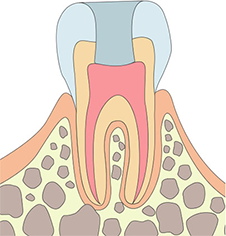

신경치료 과정

단계별 치료 과정을 통해 자연치아를 보존합니다

치근관충전

크라운치료

신경치료가 완료된 이후 치아의 파손이 삽질 우려가 변경 수 있습니다.

치아 강도가 약해지기 때문에 반드시 보철치료를 받아야 하며, 크라운이나 인레이로 치아를 보호해야 합니다.

신경치료가 끝난 이후 반드시 보철 치료가 병행 되어야 합니다.